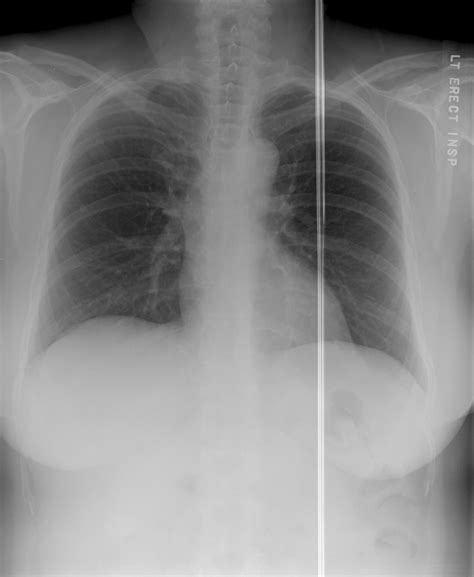

Radiography is the process of using radiation to view the internal structure of the body. It is a non-invasive procedure that allows doctors to see inside the body without surgery. The most common type of radiography uses X-rays, which are a form of electromagnetic radiation. When X-rays pass through the body, they are absorbed differently by various tissues. Dense tissues, like bone, absorb more X-rays and appear white on the image, while less dense tissues, like muscle and fat, absorb fewer X-rays and appear gray. Air-filled spaces, like the lungs, absorb the least amount of X-rays and appear black.

• Conventional Radiography: This is the most basic form of radiography, using X-rays to produce images on film or digital detectors. It is commonly used to diagnose fractures, pneumonia, and other conditions.

• Diagnostic Imaging: Radiography is primarily used for diagnostic purposes. It helps doctors identify fractures, infections, tumors, and other abnormalities. For example, a chest X-ray can reveal pneumonia, while a bone X-ray can show a fracture.